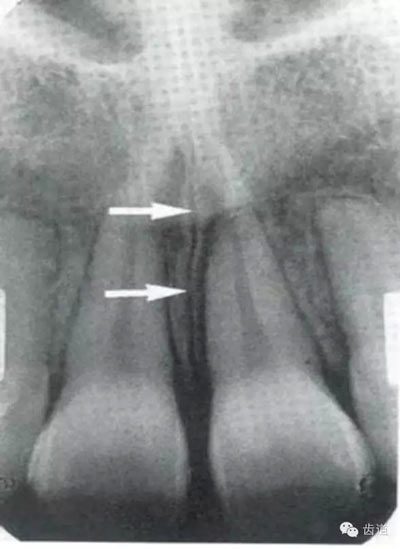

位于兩側(cè)中切牙牙根之間,由牙槽突向上,呈直線狀密度低的影像。其兩側(cè)為密度高的影像,為兩側(cè)上頜骨腭突的致密骨層。

鼻腔位于上切牙根尖的上方,顯示為對(duì)稱性半圓形密度低的影像,其中間被一密度高的骨隔分開(kāi)為鼻中隔